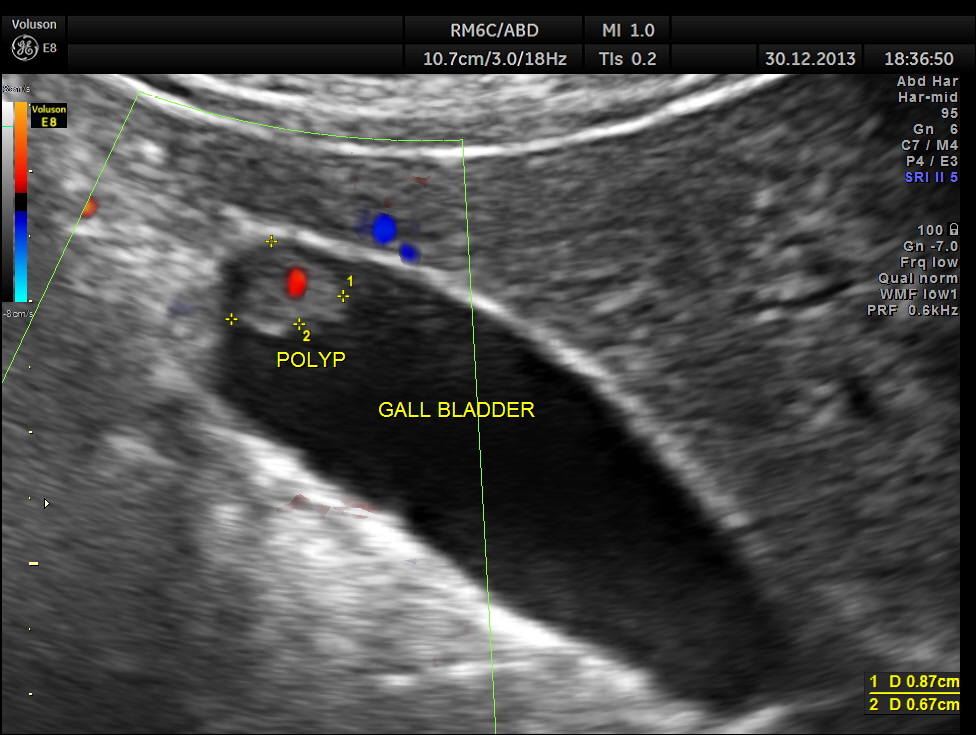

GB Polyp is seen . Colour flow imaging shows flow.

the high definition flow image is given below.